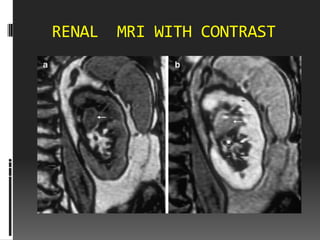

RENAL   MRI WITH CONTRAST

• #29 1-weighted gradient echo images before (a) and after (b) gadolinium administration. A mass in the renal pelvis (arrow) shows moderate enhancement after gadolin